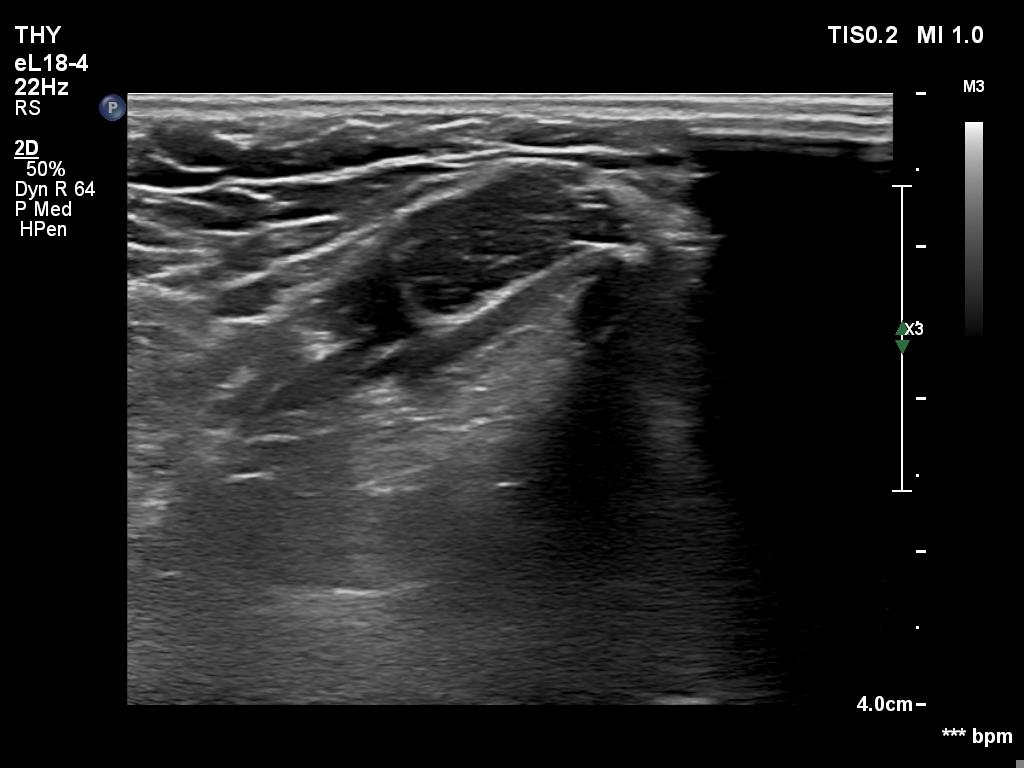

Graves' disease - case 940

Follow-up investigation 6 months after first visit (ultrasonographic picture 6)

Right lobe, longitudinal scan

Middle part of the neck, 4 cm above the thyroid, another longitudinal scan.